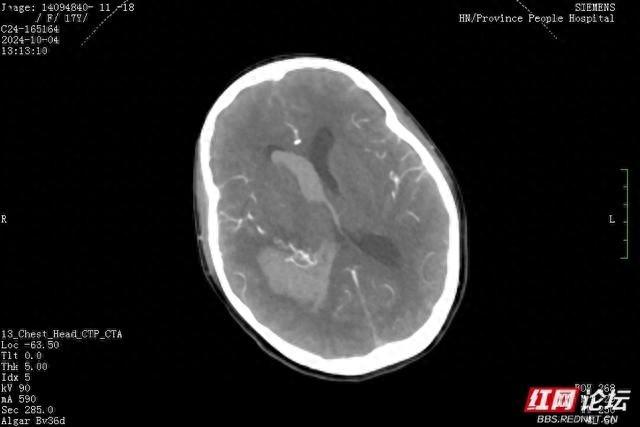

小雯抵达医院后,急诊科对她进行了头部CT扫描。结果显示,她的颅内发生了出血。不久,她被转移至神经外科一病区。经过头部CTA和DSA检查,诊断结果为“右侧颞顶枕叶脑出血破入脑室”,同时伴有“大脑血管动静脉畸形”。病情相当严重,神经外科的医生们对此高度重视,不敢有丝毫懈怠。

手术过程中,外科团队面临了严峻挑战。他们必须在清除血肿及切除血管畸形的过程中,小心避免损伤邻近的肢体运动功能区神经纤维。头部CT及CTA检查显示,血管畸形团与神经纤维紧密相邻。孙圣礼主任在手术中犹如在细如钢丝的生命线上行走,每一步都需极为谨慎,以避免对小雯造成不可逆转的伤害。